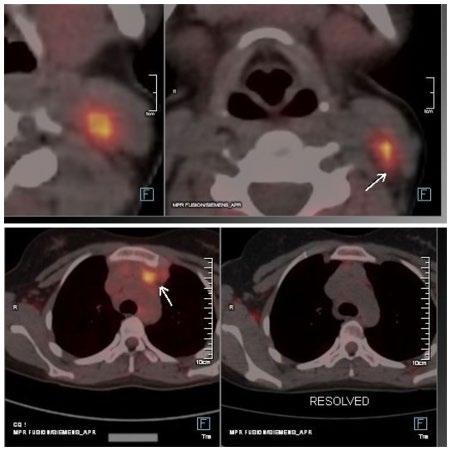

Creative Artworker

Dillon Benn Grove

Designers

Shanjok Gurung, Fabio van Paris

Junior Designer

Helena Spicer

Head of Marketing

Stephanie Corbett

Chief Executive Officer

Justin Levett